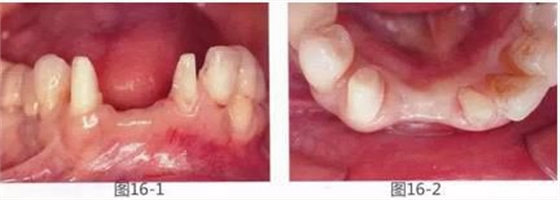

圖16-1,2 術(shù)前。有垂直以及水平牙槽嵴吸收。另外,左下2,3有深度牙周袋,附著齦也不足。